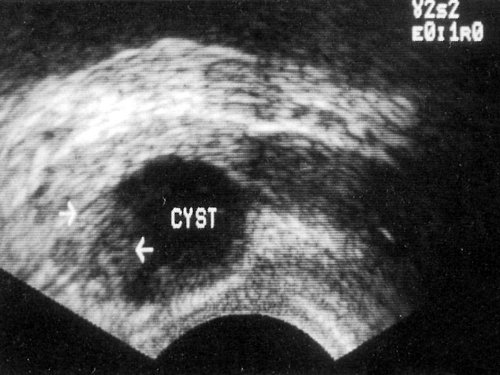

На косой поперечной сканограмме видна киста с гладкими стенками в периферической зоне.

Ретенционные кисты предстательной железы развиваются вследствие дилатации железистых долек при приобретенной обструкции мелких протоков. Они могут появиться в любой зоне предстательной железы, но наиболее часто - в периферической. В основе диагностики лежит локализация кист в периферической зоне простаты и отсутствие данных за наличие доброкачественной гиперплазии.